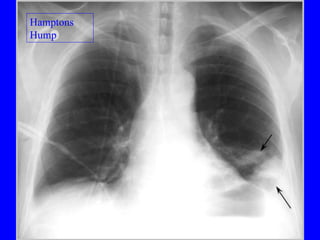

Pulmonary embolism (PE) is a common and potentially fatal condition where blood clots block arteries in the lungs. An estimated 5 million venous thromboses occur annually worldwide, with 10-30% of PE cases correctly diagnosed. Risk factors include older age, cancer, obesity, surgery, trauma, and genetic or acquired hypercoagulable states. Diagnosis involves assessing clinical probability based on symptoms and risk factors, then confirming with tests like D-dimer, chest imaging, ventilation-perfusion scanning, pulmonary angiography, or CT pulmonary angiography. Treatment focuses on anticoagulation to prevent further clotting while allowing natural lysis of existing thrombi.